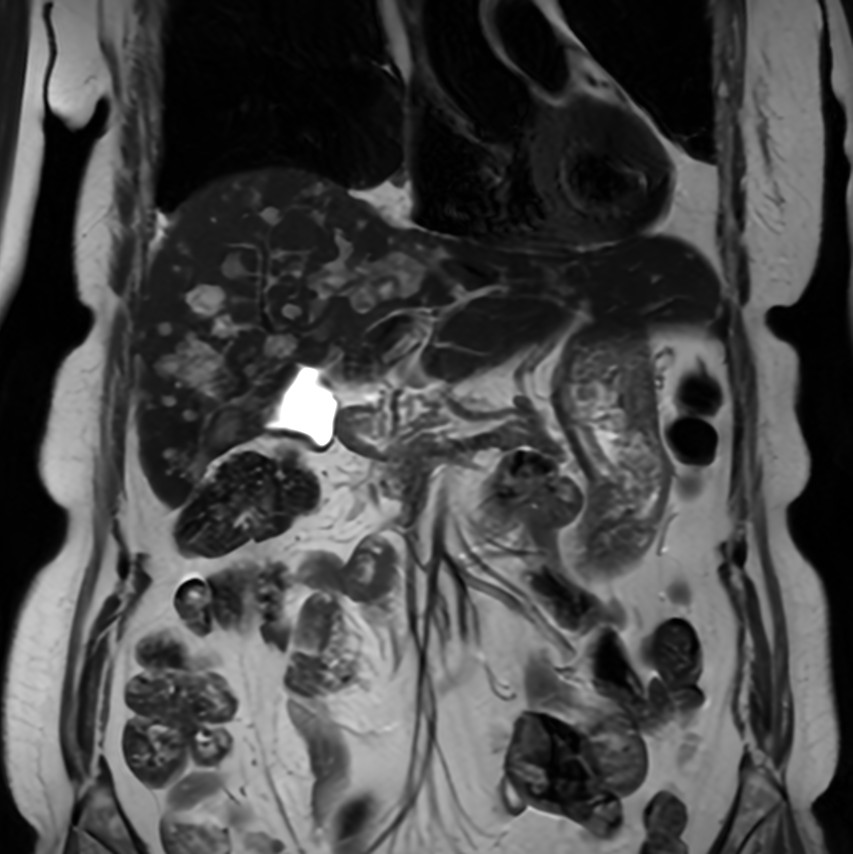

Coronal T2w SSh